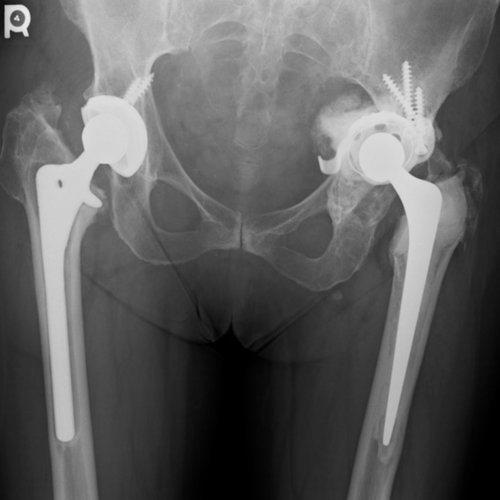

Anteroposterior (AP) radiograph of both hips showing bilateral hip replacements with polyethylene liners (it is difficult to distinguish ceramic from metal heads). The right hip stem is radiographically loose with radiolucent lines in all 7 Gruen zones.

Anteroposterior plain radiograph of the pelvis taken three years after the left hip reconstruction. There has been no migration of the cup-cage construct. Note that the right side has been revised.